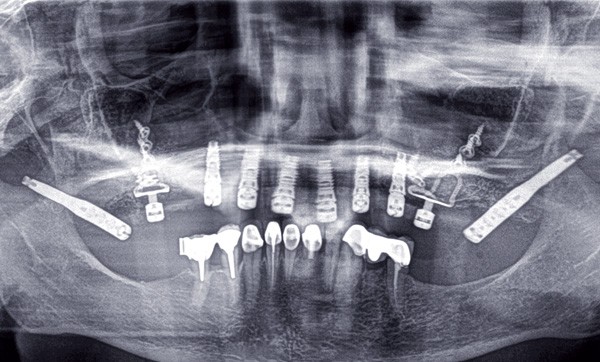

L’implantologie basale initiée par Jean-Marc Juillet [2] en 1972, et reprise en 1978 par Gérard Scortecci [3, 12, 13], est caractérisée par la pose d’implants disques spécialement conçus. Présentés officiellement pour la première fois à Munich en 1984, ces implants sont impactés latéralement à la suite d’une ostéotomie réalisée au niveau des bases osseuses dans les trois sens de l’espace à l’aide d’un cutter monté sur turbine sous spray (fig. 1). Ces Diskimplants en titane peuvent comporter d’un à trois disques de différents diamètres (circulaires ou asymétriques) et se caractérisent par un pilier intégré présentant un hexagone externe protégé par un carénage cylindrique conique [4, 7, 8].

En implantologie basale, les critères de succès de l’ostéo-intégration sont les mêmes qu’en implantologie axiale [5, 6, 18, 19]. La maîtrise du geste opératoire représente la difficulté majeure de la méthode. Un apprentissage s’appuyant sur un enseignement encadré est donc nécessaire. Il aboutira en France en l’obtention d’un diplôme universitaire délivré par la Faculté de Médecine de Nice-Sophia Antipolis.